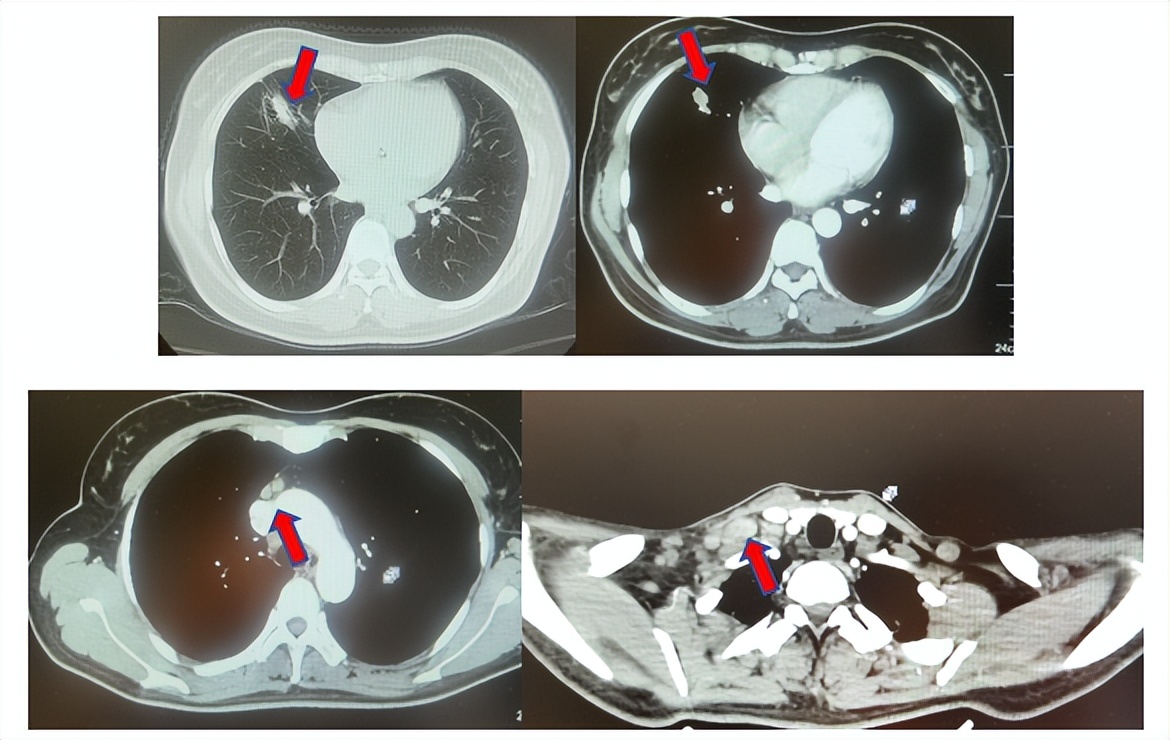

2.2影像学检查(图5)

肺+全腹CT增强:右肺中叶肿块,考虑恶性,双肺胸膜下炎症,双侧胸膜局限性增厚,右侧锁骨上淋巴结增大,纵隔淋巴结稍大;

颈部CT增强:右侧锁骨上及右颈部、纵隔多发淋巴结肿大。

图5:上两图分别展示基线时肺CT肺窗及纵隔窗右肺中叶病灶影像,下两图表示基线状态时纵隔淋巴结及锁骨上淋巴结影像。

患者符合我科正在开展的一项“评估信迪利单抗或安慰剂联合培美曲塞和铂类化疗用于晚期或复发性肺鳞状细胞非小细胞肺癌一线治疗有效性和安全性的随机,双盲,III期研究(ORIENT-11)”临床研究入组条件,应用信迪利单抗或安慰剂联合培美曲塞+卡铂治疗4周期,信迪利单抗或安慰剂联合培美曲塞维持治疗13周期,后应用信迪利单抗或安慰剂应用至2年。试验结束后出组,揭盲患者为信迪利治疗组。治疗期间最佳疗效肺内病灶近CR(图6)。停药后每3个月-6个月复查随访,未见肿瘤复发转移征象(图6),截止至目前为止,一线无进展生存已超过75个月。

图6:上三图分别展示2019年6月患者达到最佳疗效时肺CT肺窗及纵隔窗右肺中叶病灶及锁骨上淋巴结影像,下两图表示2025年2月患者最近复查评效时肺CT肺窗及纵隔窗肺内病灶影像